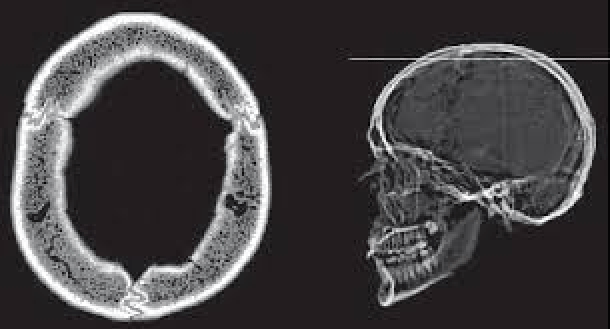

Tomografia Computerizzata Tc Nelle Malattie Neurologiche Malattie Neurologiche Manuali Msd Edizione Professionisti

Tomografia Assiale Computerizzata Tac Tc Anircef

Tac Tomografia Assiale Computerizzata

Tc Encefalo Che Cos E Sintomi Cause Prevenzione E Trattamento Top Doctors

Tac Tc Cranio Senza Mezzo Di Contrasto Artemisia Lab

Tecniche Di Diagnostica Per Immagini In Neurologia